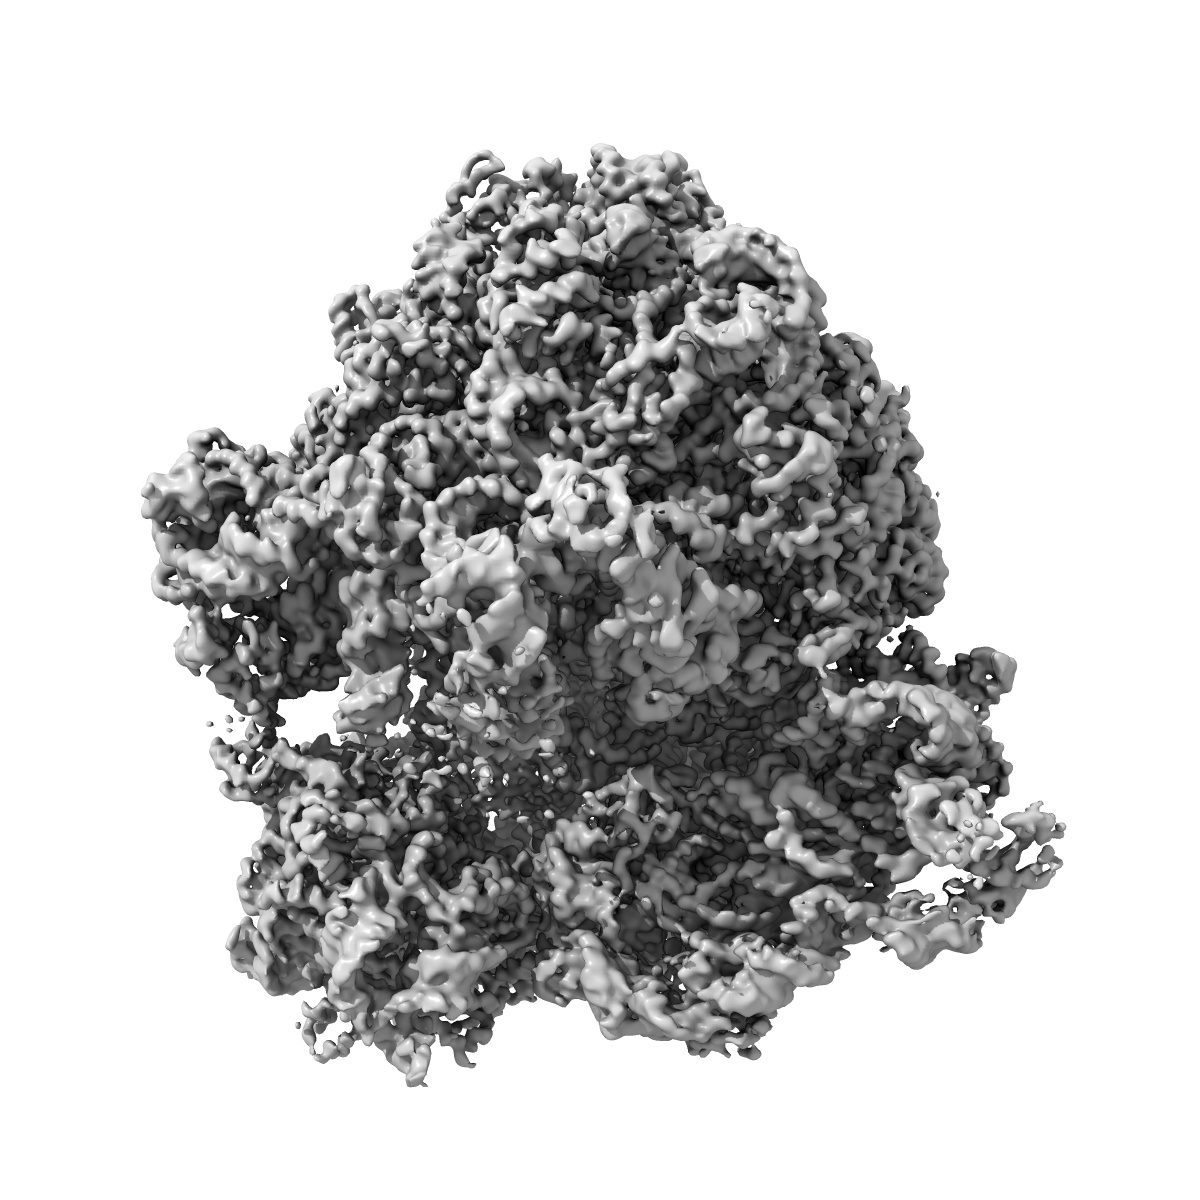

E. coli 70S ribosome in complex with dirithromycin, and deacylated tRNA(iMet) (focused classification).

Single-particle2.66 Å

Sample: E. coli 70S ribosome in complex with dirithromycin and deacylated tRNA(iMet).

Insights into the improved macrolide inhibitory activity from the high-resolution cryo-EM structure of dirithromycin bound to the E. coli 70S ribosome.

(2020) RNA , 26 , 715 - 723